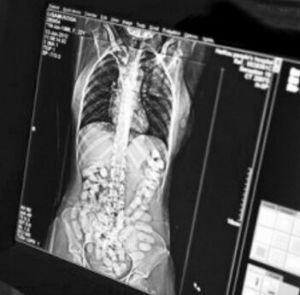

該女子交代其於8月30日吞食毒品海洛因78粒,從成都乘坐K452次列車前往吐魯番,打算在吐魯番站中轉去石河子,9月1日,列車即將到達吐魯番站時,因身體不適,在火車廁所里排出毒品海洛因8粒,因時間緊迫來不及清洗,遂將其暫時放置在內褲中,不料下車後就被民警現場查獲。得知其體內還有毒品後,民警擔心該女子體內海洛因破裂,遂立即將其帶至吐魯番市醫院進行X光檢查,經檢查發現該女子腸道記憶體在大量塊狀物,經工作,該女子又陸續多次從體內排出毒品海洛因70粒,總計78粒。